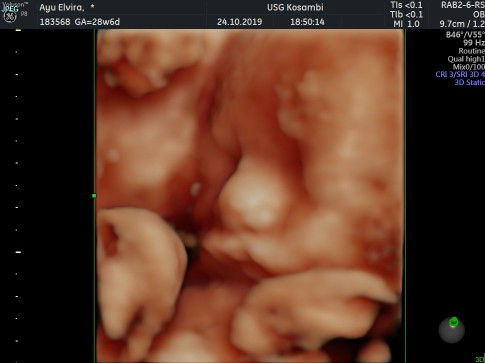

Assalamualaikum Bun ... Cuma mau sharing aja .. Tadi malam saya USG 4D dokter bilang janin saya baru 26 week.. jelas saya kaget sebelum nya saya USG di rumah sakit bulan Agustus dokter bilang sudah 4 bulan otomatis bulan ini saya mau masuk kandungan 7 bulan .. gimana ya Bun saya hitung Hari terakhir haid 5 April tapi kenapa dokter itu bilang saya baru 26 week?